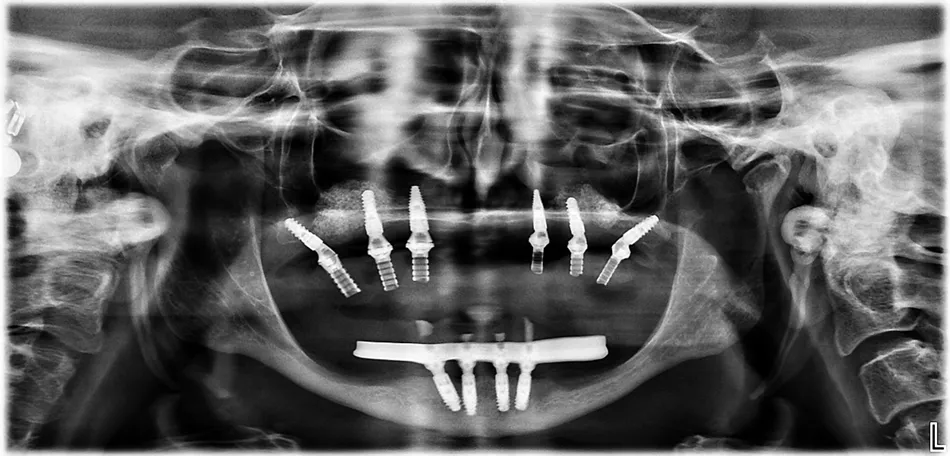

Figs. 31,32 Panoramic radiograph showing the final position of the implants: Two BLX implants placed in the maxillary tuberosities, two BLX implants in the grafted sinus areas (left and right), and two BLC implants in the anterior maxilla adjacent to the sinus wall.

Figs. 60-62 Final panoramic radiograph showing the implant rehabilitation: BLX implants in the maxillary tuberosities and grafted sinus, BLC implants in the anterior maxilla, and TLX NT implants supporting the mandibular restoration. Note also the horizontal CBCT views demonstrating good integration and adequate anteroposterior (AP) spread of the implants.